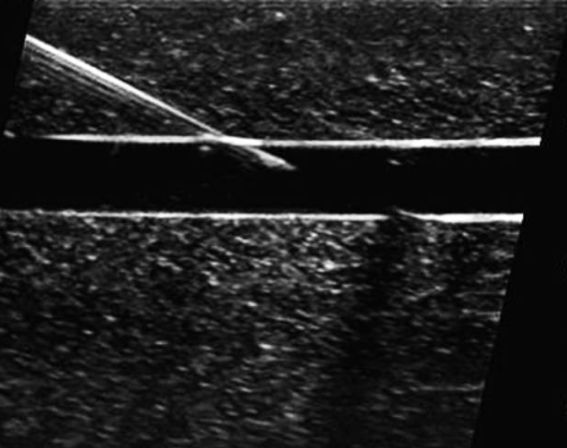

平面内穿刺的优势在于整个针体(包括针尖)可视化,但是对操作者手法技巧(始终保持探头长轴与血管长轴平行)要求较高,易受解剖结构限制。

平面内穿刺的超声图像。